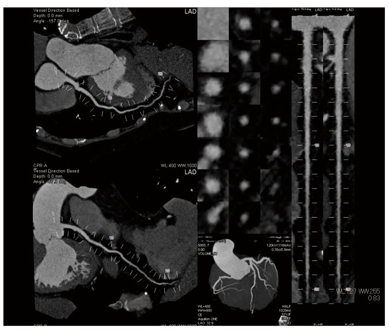

ziostation2からPACSへ転送する画像は、VR、AngioView、CPR、ストレッチMPR、MPR Axialである。VRは、入口部や全体が見えるように15枚程度作成している。AngioViewは、RAO、RAO CAUDAL(以下CAU)、CAU、CRANIAL(以下CRAN)、LAO CRAN、LAO、LAO CAUの7Viewを分岐良く描出している。残りのCPR、ストレッチMPR、MPR Axialは、VGRに入っている組み合わせ画像出力を使用している。この出力方法はいくつかの組み合わせがあるため、各施設が必要な画像を選択し出力することができる。当院の出力画像を図3に提示する。

ステントや石灰化の強いところ、プラークなどのしっかり評価したいところは、MPRにて細かくshort Axialやlong Axialなどを作成しPACSに送信している。

図3 PACS転送している出力画像